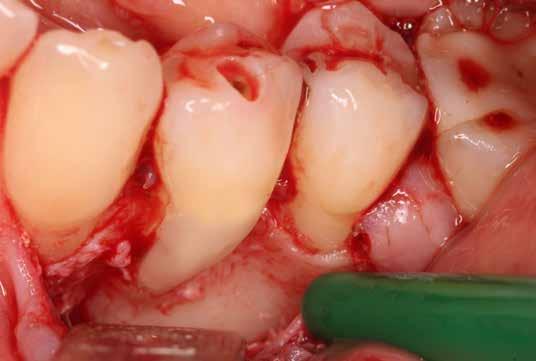

12. kép: Trepanálás és lebenyalakítás. – 13. kép: A gyulladásos szövet eltávolítása után a kavitás kiterjedése jól láthatóvá vált.

14. kép: Kofferdam izolálás és a gyökércsatorna kiblokkolása guttapercha segítségével.

15. kép: A fog restaurálására mikro-hibrid kompozit tömőanyagot alkalmaztunk.

16. és 17. kép: Lebenyzárást követően befejeztük a fog gyökérkezelését. – 18. kép: 2 hónapos kontrollon a fog és az íny állapota is rendben.

kép]. Az üregben nagy mennyiségű gyulladásos szövetet találtunk, mely eltávolítása után láthatóvá vált a kavitás kiterjedése [13. kép]. A kisőrlő fogakra jellemző tengelyirányú, valamint oldalirányú terhelés kombinációja, valamint a je-

lentős foganyagveszteség miatt szerettük volna a lehető legjobban megerősíteni a fogat. A terület kofferdám gumilepedővel történő abszolút izolálása után a gyökércsatornát egy guttapercha segítségével kiblokkoltuk, ezzel megelőzve

a csatorna obliterálódását [14. kép]. Ezután megfelelő adhezív előkezelést követően kompozit tömőanyaggal restauráltuk az elváltozást (Essentia Universal, GC Europe) [15. kép]. Finírozást és alapos polírozást követően zártuk lebenyünket, majd újabb kofferdám izolálásban elvégeztük a fog gyökérkezelését [16. és 17. kép]. A kezelést követően páciensünk teljesen panaszmentes volt. Két hónapos kontrollon a fog teljesen ép, az íny tökéletes kitapadását tapasztaltuk [18. és 19. kép] Szondázási mélység a bukkális oldalon mindenhol 2 mm alatt volt.